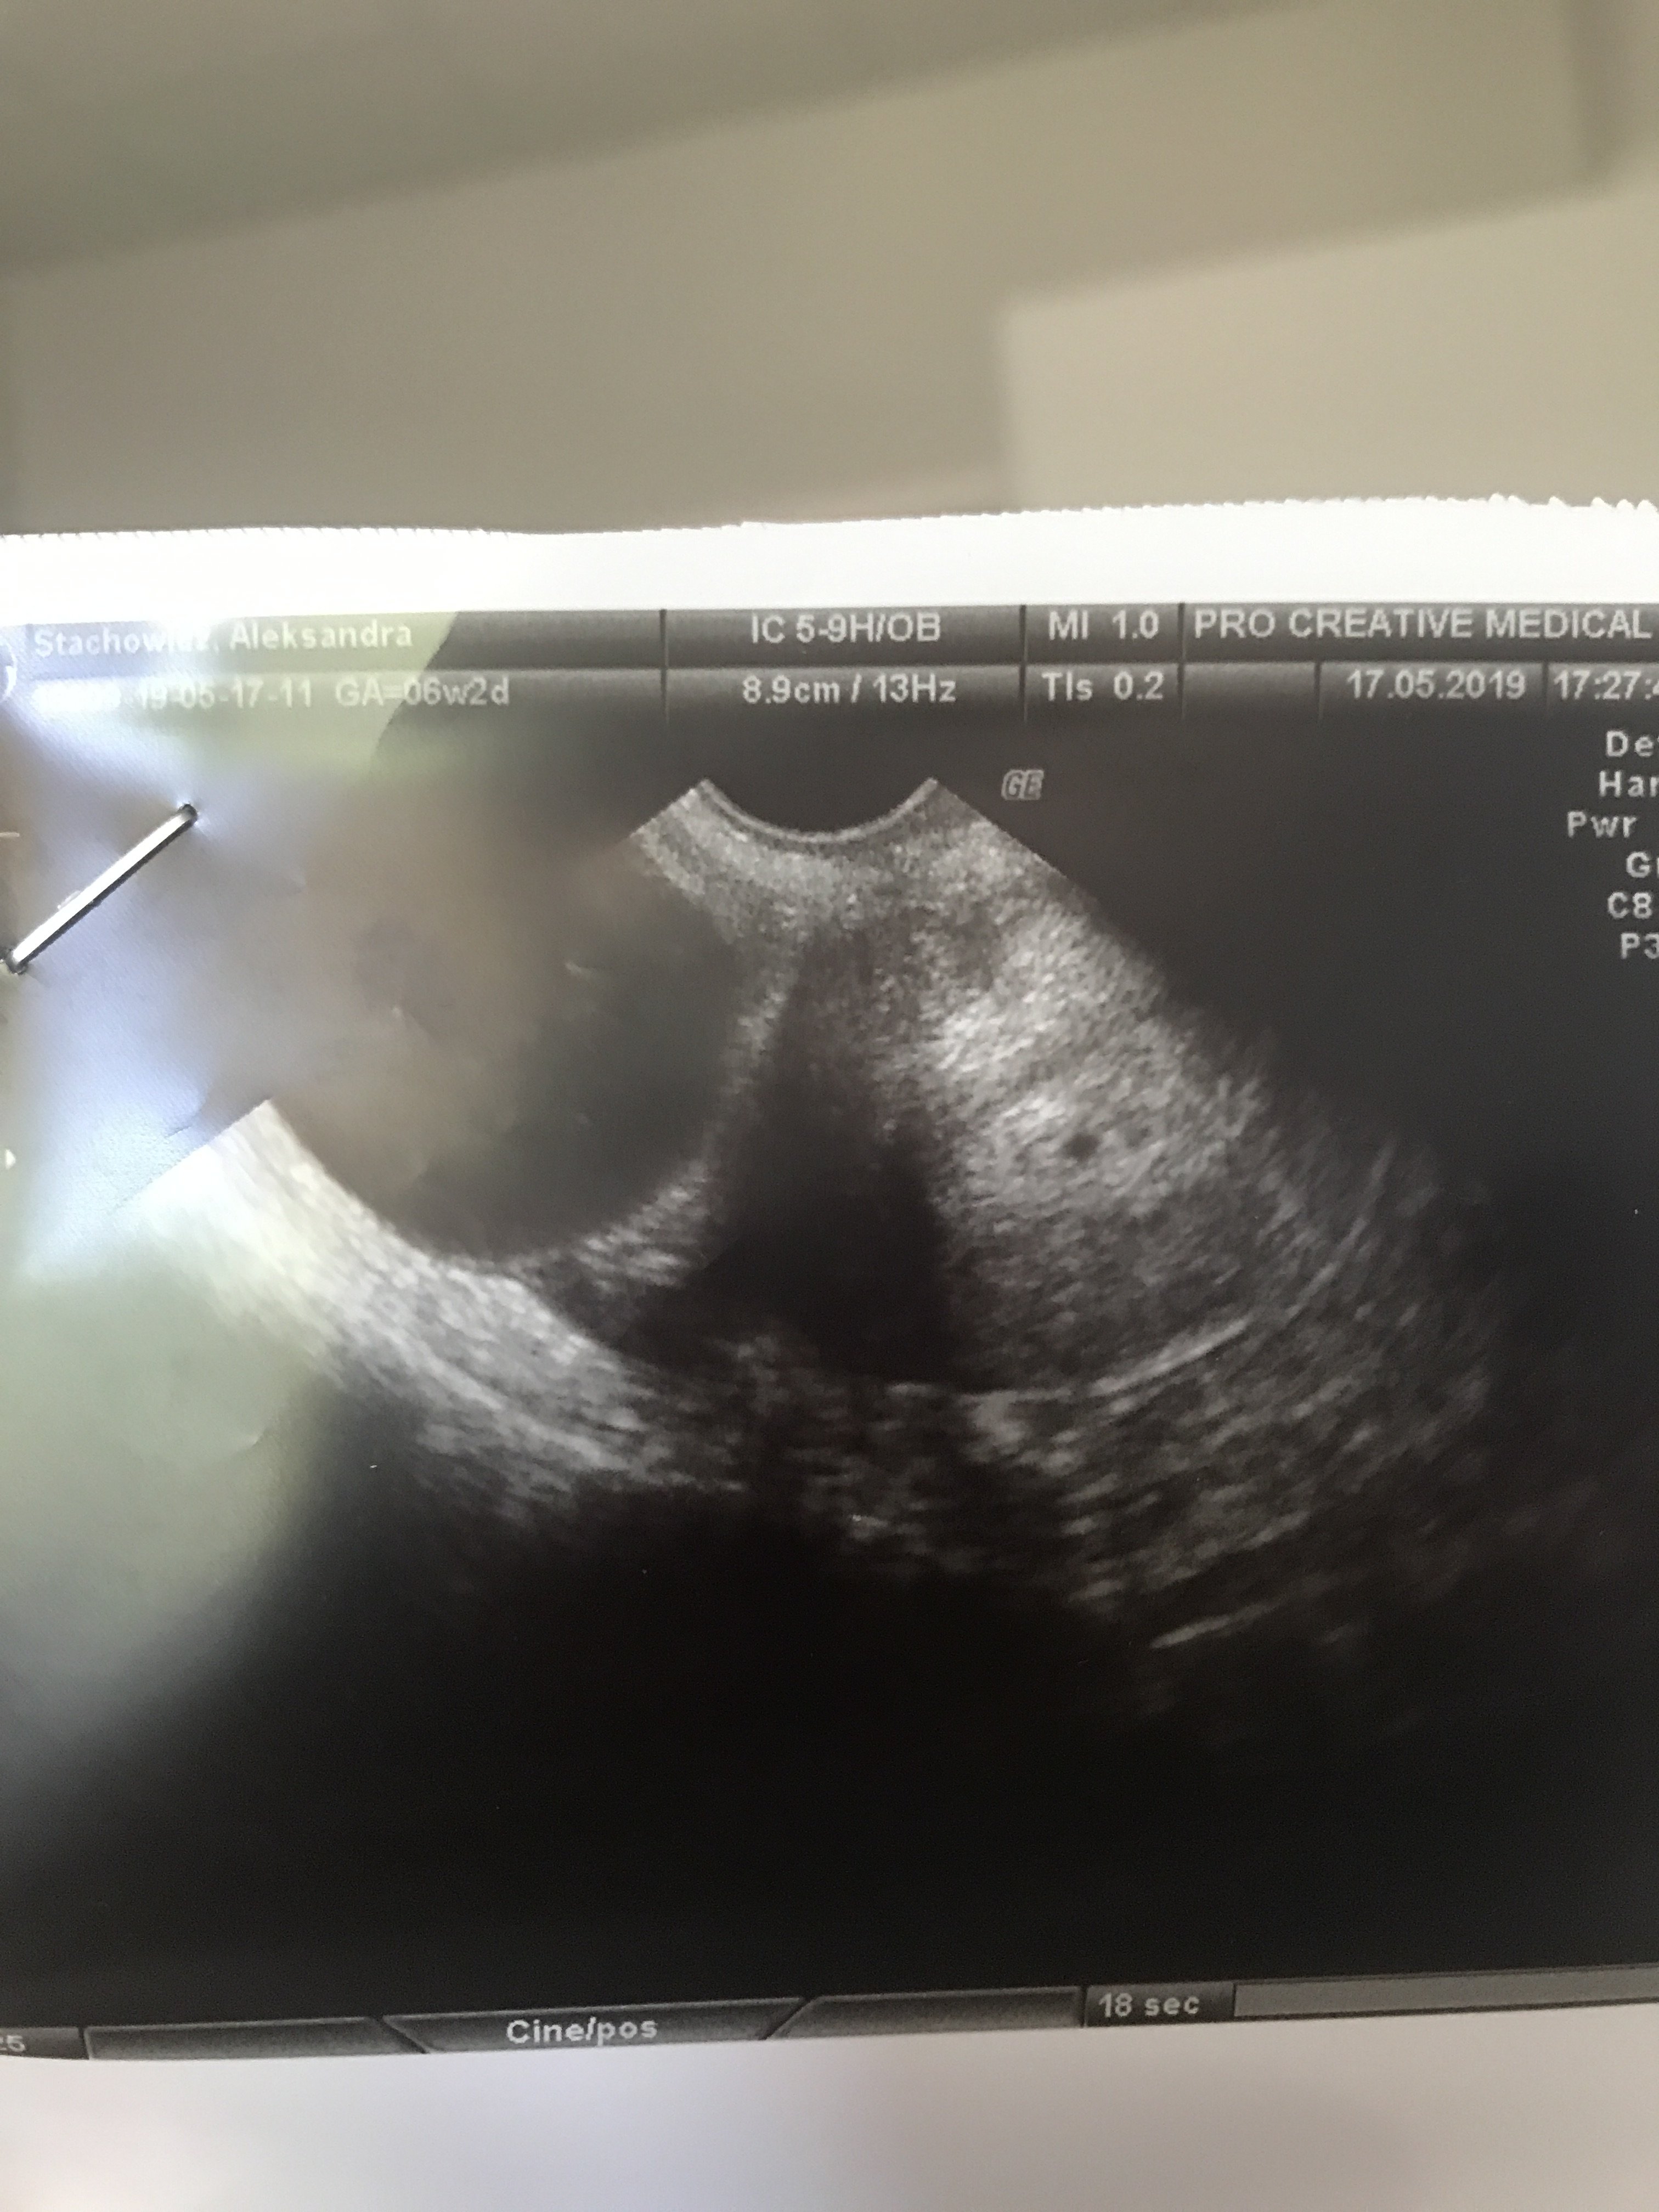

11.07 miałam @test ciążowy wychodził mi pozytywny już w 24dc. Zrobiłam bete: 26dc 95, 28dc 294, 31dc 1148 (godz 18.00), 33dc 2250 (godz 8:30). Wczoraj byłam u lekarza, według om byl to 5tc+5 a z usg 5tc+2. Widoczny był tylko pęcherzyka i zmartwilam się że nic więcej nie zobaczył mimo że owulacje miałam w 13/14dc. Mam przyjść za tydzień, ale trochę się podlamalam. Czy ktoś miał podobna sytuacje? Czy mimo wzrastającej wcześniej bety ich może się teraz ciąża nie rozwijać prawidłowo czy to za wcześnie na zarodek?

Kochana, niczym się nie stresuj, wszystko wyglada ok. Ja miałam podobna sytuację- według obliczeń na 1usg ciąża powinna być już w 6tyg+3,a widać było jedynie malutka kuleczkę i wielkie „coś” na jajniku. Zostałam wysłana w trybie natychmiastowym na obserwacje pod katem ciąży pozamacicznej. Okazało się ze mam wielka torbiel, a ciąża po prostu była młodsza i był to dopiero początek 4 tygodnia. Głowa do góry, wszystko będzie ok!

• 72DB38D3-DE1B-4822-8D9D-4527777BE447.jpeg

1,1 MB · Wyświetleń: 193